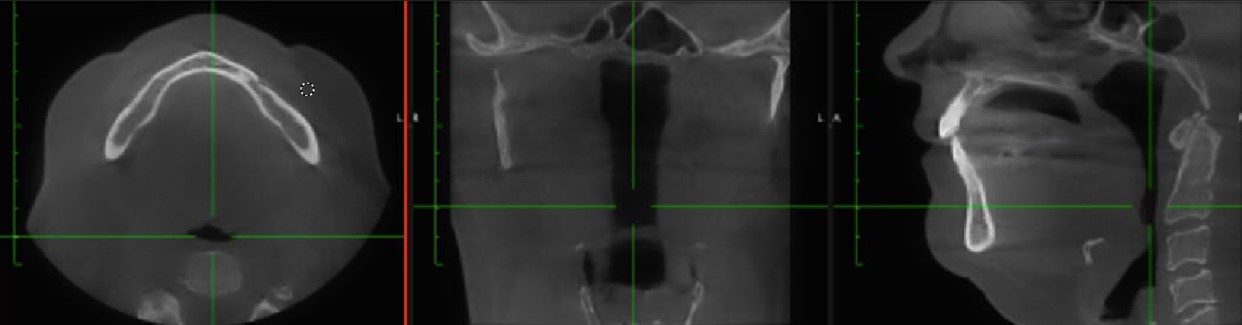

Airway and CBCT Improvements:

Posttreatment CBCT, cephalometric and Schwartz model analysis revealed:

• AHI reduced from 41.7 to 9 events/hour

• Supine AHI: 51.9 to 0 events/hour

• Oxygen desaturation index: 21.3 to 4

• O2 saturation nadir: 81% to 93%

Arch Width and Oral Volume Increase (Schwartz Model Analysis):

• Premolar width (mesial pit #5–#12): 30.86 mm → 36.81 mm (+5.95 mm) (Figure 9)

• First molar width (#3–#14): 40.59 mm → 46.24 mm (+5.65 mm) (Figure 8-9)

• VDO increase: 5.28 mm (Figure 11)

• Oral volume increase: estimated at 25 mm²

• No signs of dental tipping postexpansion (Figure 8-9)